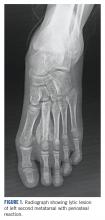

She received 3 cycles of a MAP (highdose methotrexate, doxorubicin, and cisplatin) regimen as neoadjuvant chemotherapy. Response assessment scans showed partial response (Figures 3A and B) . We performed a wide excision of the second and third metatarsal with reconstruction using a segment of non-vascularized fibular graft as rigid fixation (Figure 4) . The postoperative period was uneventful. She was able to begin partial weight bearing on the fourth postoperative day and her sutures were removed on the twelfth postoperative day. She received adjuvant chemotherapy following surgery. The final histopathology report showed residual disease with Huvos grade III response (>90% necrosis) with all margins negative for malignancy (Figure 5). At present, the child is disease-free at 5 months of treatment completion and is undergoing regular follow-up visits.